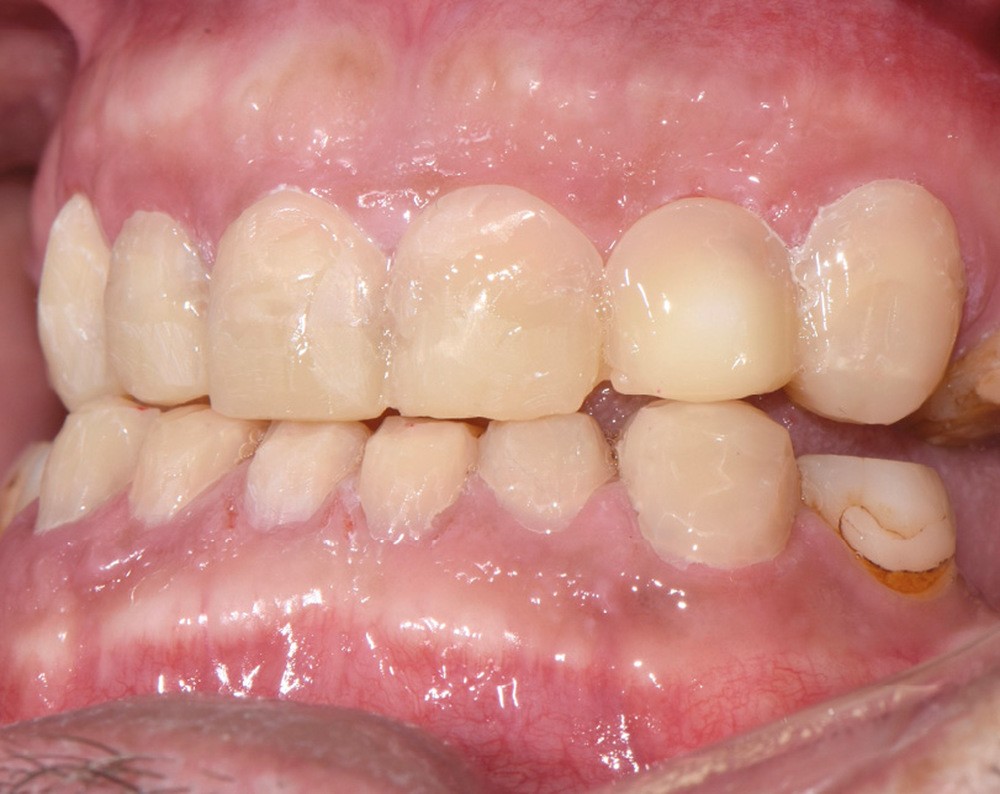

Au vu du contexte para-fonctionnel et de l’étendue de la perte tissulaire, des coiffes périphériques minimalement invasives ont été choisies afin de restaurer l’esthétique et la fonction. Actuellement, aucun consensus n’est fait sur le choix du matériau d’infrastructure à privilégier. Les matériaux hybrides usinables présentent des propriétés mécaniques, physiques et biologiques intéressantes en contexte d’usure sévère (e.g., module d’élasticité, résistance à la propagation de fêlures, facilité de réintervention). Une réhabilitation globale avec remontée de dimension verticale d’occlusion (DVO) par l’intermédiaire de coiffes composites renforcés en nano-céramiques est décrite.